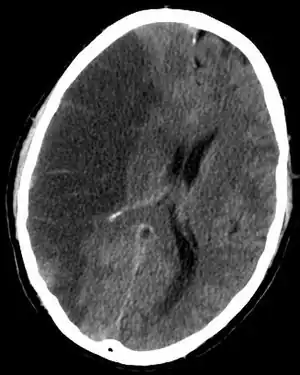

Scanner cérébral montrant un accident vasculaire cérébral ischémique de l'hémisphère droit (partie sombre à gauche de l'image).

Le scanner crânien est fait, sauf contre-indication, avec injection d'un produit de contraste iodé. Si l'accident est ischémique, il permet de visualiser la topographie, l'étendue et le nombre de lésions. S'il est hémorragique, il en fait le diagnostic.